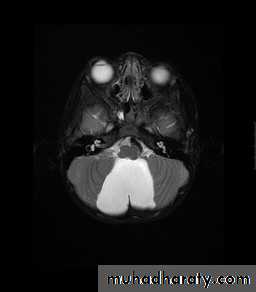

Suprasellar Arachnoid Cyst

CT Brain

MRI Brain